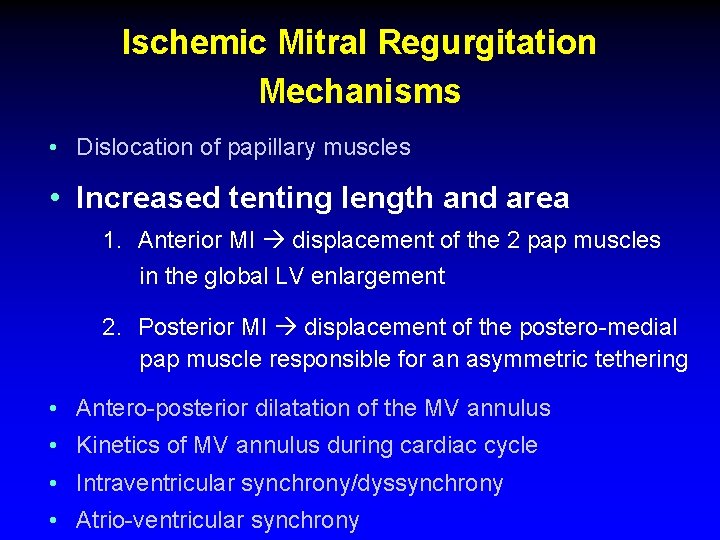

Ischemic Mitral Regurgitation Mechanisms • Dislocation of papillary muscles • Increased tenting length and area • Antero-posterior dilatation of the MV annulus • Kinetics of MV annulus during cardiac cycle • Intraventricular synchrony/dyssynchrony • Atrio-ventricular synchrony

Ischemic Mitral Regurgitation Mechanisms • Dislocation of papillary muscles • Increased tenting length and area 1. Anterior MI displacement of the 2 pap muscles in the global LV enlargement 2. Posterior MI displacement of the postero-medial pap muscle responsible for an asymmetric tethering • Antero-posterior dilatation of the MV annulus • Kinetics of MV annulus during cardiac cycle • Intraventricular synchrony/dyssynchrony • Atrio-ventricular synchrony